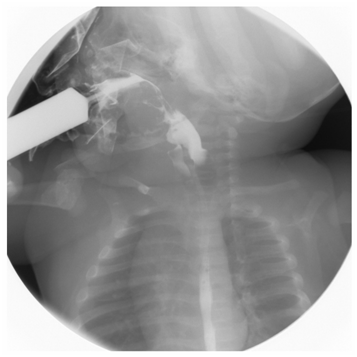

The swallowing study at diagnosis showed slow oral transit, abnormal anterior/posterior tongue movements, 5 events of pharyngonasal reflux, alteration of the epiglottic fold, bolus laryngeal penetration, barium aspiration to the upper third of the trachea, at least in the upper 2 cm, and leakage through the tracheal walls to carina, which was almost completely expelled by the cough reflex (Figure 3). BAEP were within normal limits.9 Neurological and developmental findings during follow up are summarized in Table 3.

Figure 3 Swallowing study at 2 months of age shows tracheal aspiration of the barium solution.